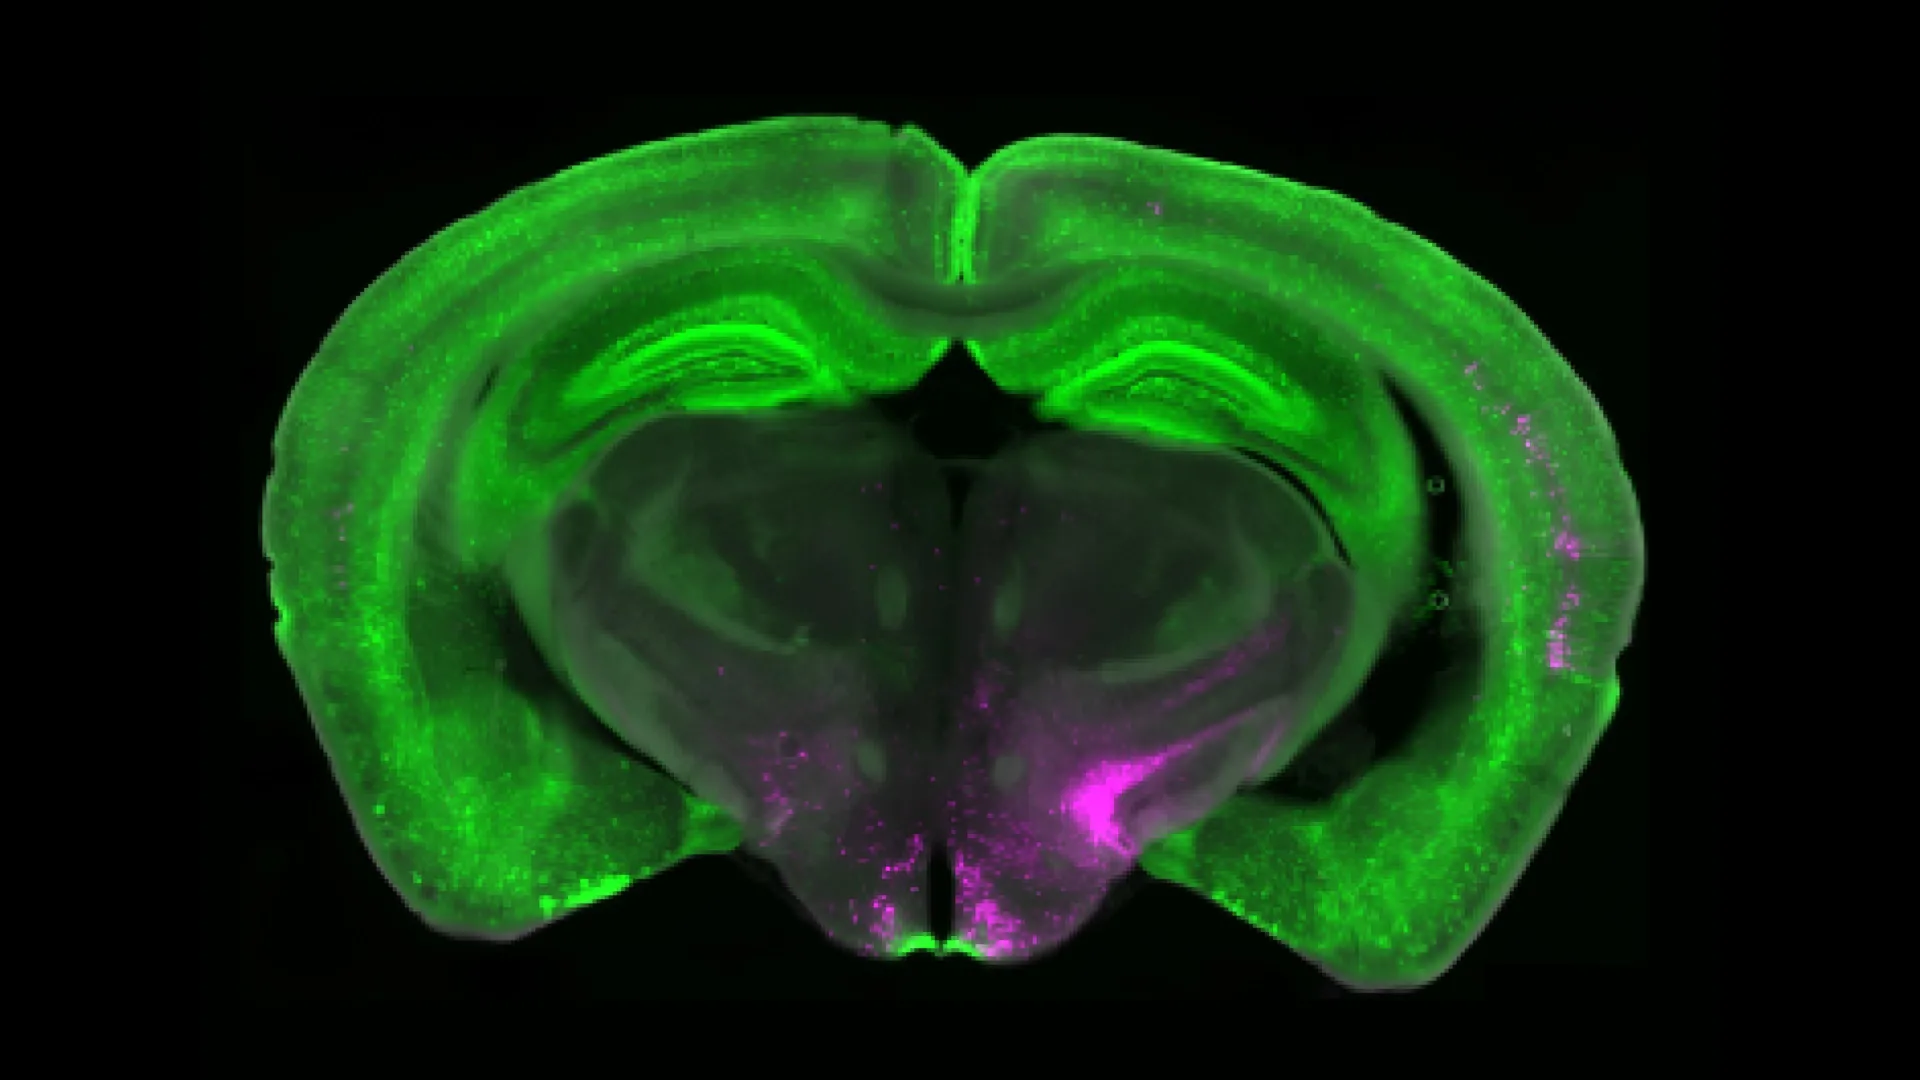

Betley cùng đồng nghiệp ở Đại học Pittsburgh và Viện Nghiên cứu Scripps phát hiện nhóm nơron biểu hiện thụ thể Y1 (Y1R) trong nhân parabrachial bên (lPBN) – trung tâm xử lý tín hiệu đau và các trạng thái sinh tồn như đói, khát, sợ hãi. Khi các nhu cầu sống còn được kích hoạt, NPY (neuropeptide Y) được giải phóng lên thụ thể Y1, ức chế hoạt động tonic duy trì tín hiệu đau dài hạn.

Fluorescent imaging of NPY+ neurons (green) and magenta projections to the PBN. Credit: J Nicholas Betley

Betley so sánh hoạt động tonic của Y1R như động cơ vẫn nổ dù xe đã đỗ: tín hiệu đau tiếp tục dù cơ thể đã hồi phục. Quan sát qua kỹ thuật calcium imaging cho thấy Y1R không chỉ phản ứng với cơn đau ngắn mà luôn duy trì tín hiệu khi đau kéo dài.